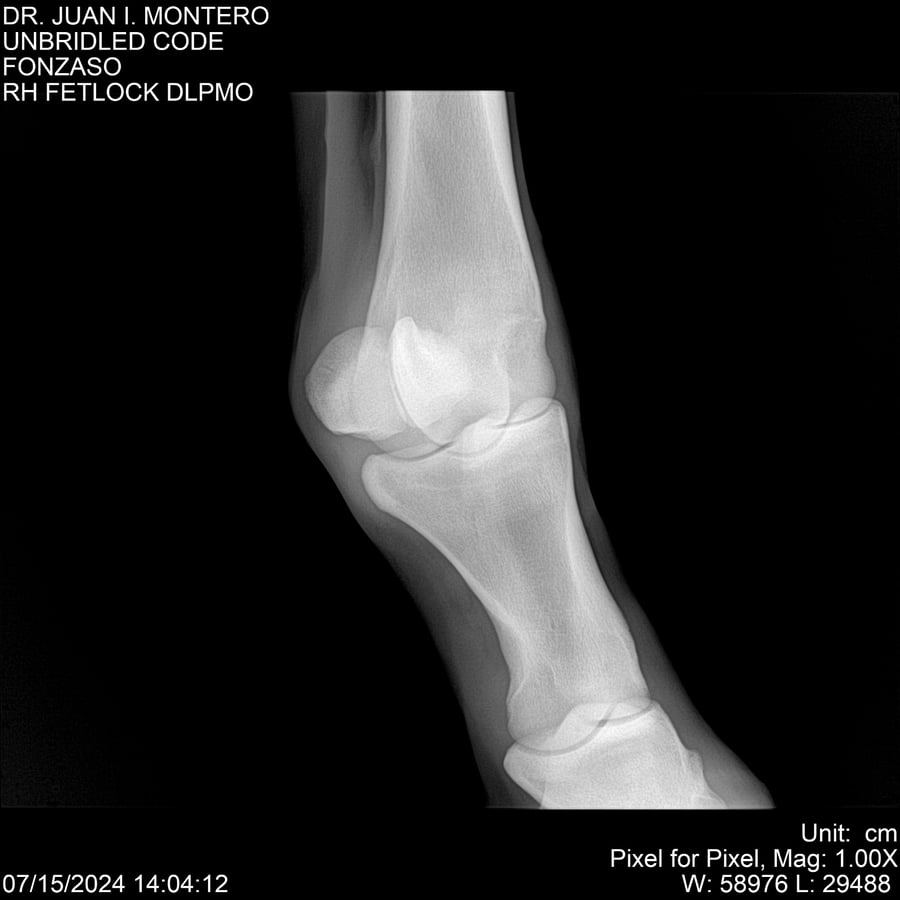

• Empresa: Abelenda N. R., Walter Hugo